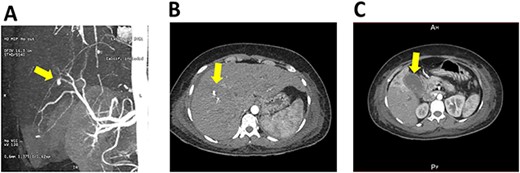

Based on the patient’s history of liver trauma and current clinical presentation, an intrahepatic vascular injury was suspected. A CT angiography was performed and revealed the presence of a saccular hepatic pseudoaneurysm measuring 5.1 × 4.4 mm in the distal-third of the right hepatic artery (Fig. 1A). The CT scan also showed dilation of the intrahepatic bile duct with a dense image inside, which was consistent with bleeding in the biliary tree (Fig. 1B). In addition, the scan showed a gallbladder with thickened walls and radio dense images inside, compatible with the presence of stones (Fig. 1C).

CT scan and angiography of hepatic pseudoaneurysm; (A) saccular hepatic pseudoaneurysm measuring 5.1 × 4.4 mm in the distal-third of the right hepatic artery; (B) the CT scan also showed dilation of the intrahepatic bile duct with a dense image inside, which was consistent with bleeding in the biliary tree; (C) gallbladder with thickened walls and radio dense images inside, compatible with the presence of stones.